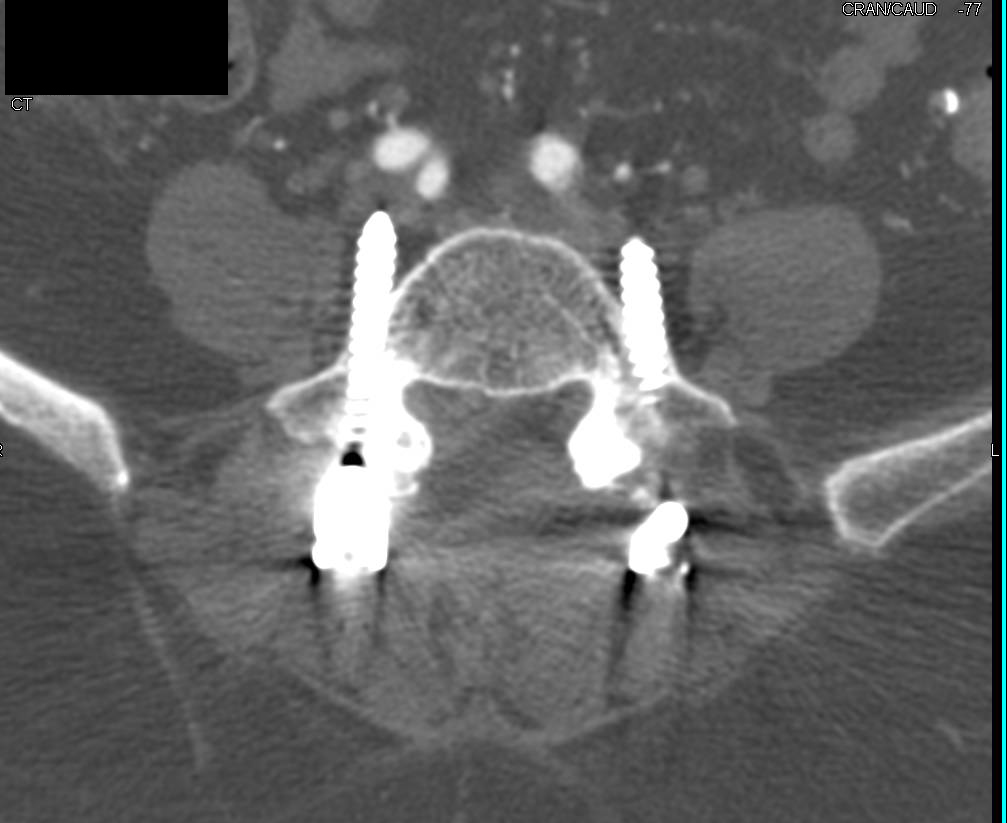

Diagnosis

Complex Repair of Ascending Aorta, Arch and Root with Reimplantation of the Coronary Arteries